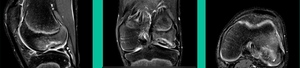

43-Year-Old, symptomatic medial femoral condyle.

D1 football player formally, affecting ADLs. For this one, I initially just wanted to watch it. This looks pretty small when he came in. Let’s see what happens. Six months later, this is where he progressed to.

We get in there, it’s delaminated, not much bone, nothing to fix in my mind, and so we drilled it.

How do these do? There’s actually reasonable data for marrow stimulation for OCD. But if you have the option for small defects, I would prefer an osteochondral allograft over microfracture based on the literature. That’s the take-home. Marrow stimulation, if you do it, you’re probably better off drilling it. We showed that we could reduce revision rates with marrow stimulation by two-thirds if you drill it versus use a microfracture awl.